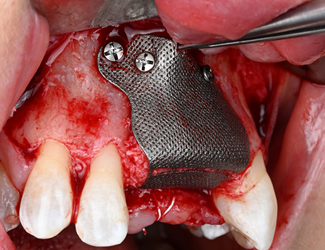

Yngre kvinna som genom trauma förlorat tänderna 11-22. En både horisontell samt vertikal defekt i ett estetiskt utmanande område. Ett Yxoss 3d printat membran framställs genom planeringsverktyget, i detta fall IO scan samt CBCT som underlag. En pre-protetisk uppvaxning på tänkt suprakonstruktion framställs för att förutsäga kommande protetik samt tänkt benvolym. Partikulerat ben appliceras i membranet som sedan fixeras på plats. Efter 6 månaders läkning avlägsnas membranet. Regenererat ben med obefintligt pseudoperiost påvisas, implantat kan placeras med god marginal samt goda protetiska förutsättningar.

Yxoss membran fyllt med partikulerat autologt ben samt Geistlich Bio-Oss

Fixerat Yxoss membran